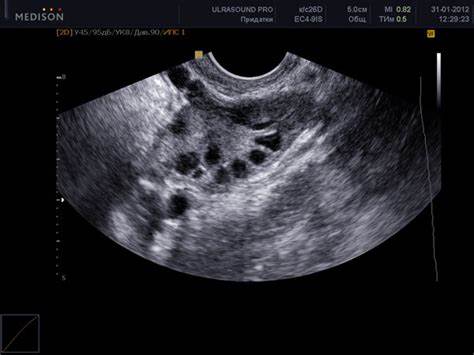

Картинка 8: УЗИ яичников